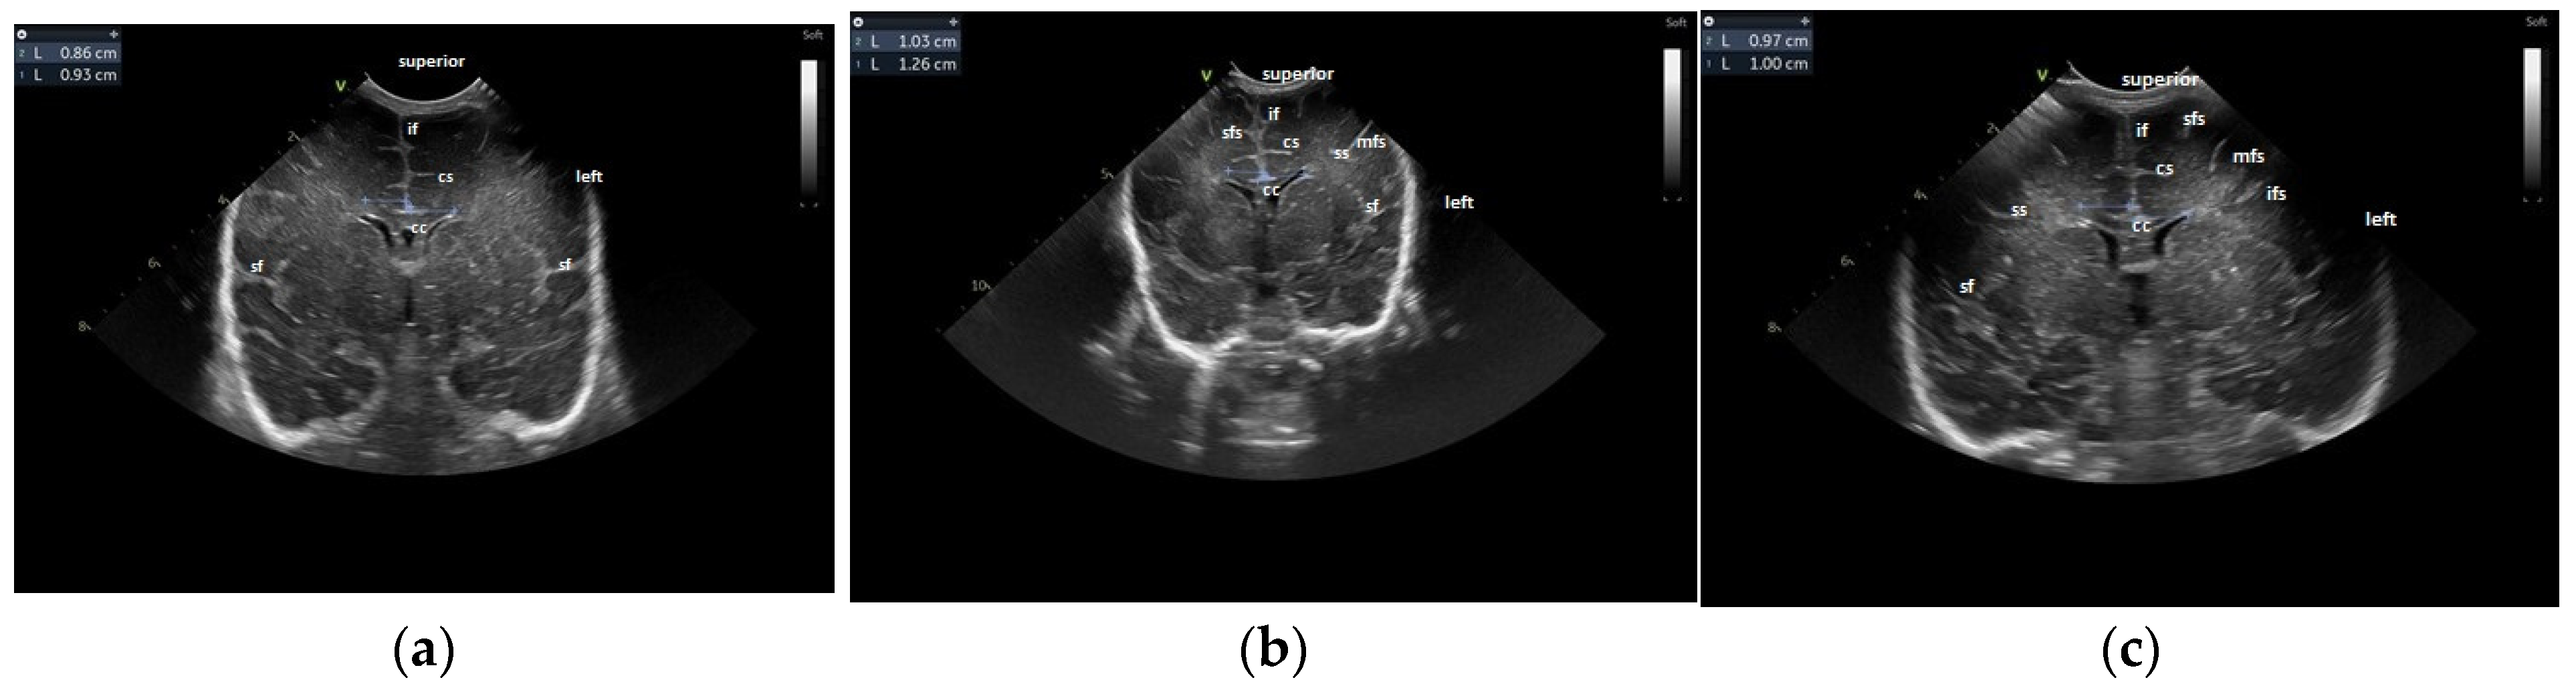

- The gyral maturation pattern—evaluated in 3 sections—coronal at the level of the foramen of Moro—looking at the Sylvian fissure and the depth of the sulci: sagittal—looking at the frontal gyri and sulci and the presence of the central/marginal sulcus and parasagittal, temporal, at the level of the insula [39]. The cortical gyral maturation was assessed according to previously published scores [15,20], and to know patterns of sulcal and gyral maturation [21,22], divided into three categories: